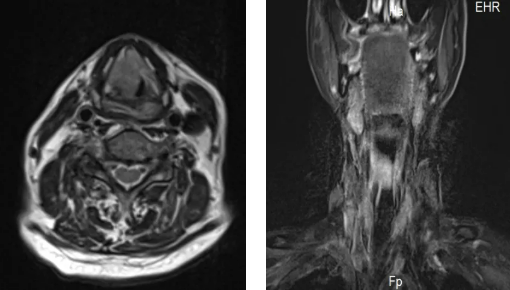

84歲的趙大爺因喉部腫瘤,三個(gè)月前做了氣道改造手術(shù),平時(shí)靠一根氣管套管輔助呼吸。沒想到一天深夜,這根“生命管”突然脫落,頸部的人工氣道口也很快閉合。老人呼吸困難,被家人緊急送往隨州市中心醫(yī)院。 情況萬分 ...